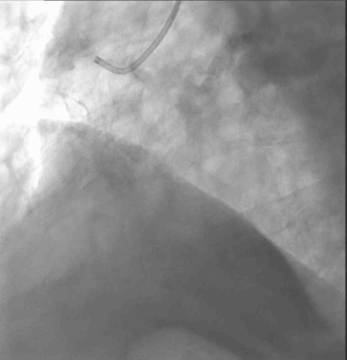

主动脉根部造影提示瓦氏窦整体形态较大,无冠瓣瓣叶钙化斑块程度较重。

瓣膜展开后与术前策略讨论的风险预期相符,受无冠瓣较重钙化和瓣上结构整体的影响,瓣膜释放后的腰部形态受限,决定使用25mm球囊后扩治疗。

最终瓣膜形态和位置良好,造影无明显瓣周漏和返流。

术后平均跨瓣压差降至6mmHg